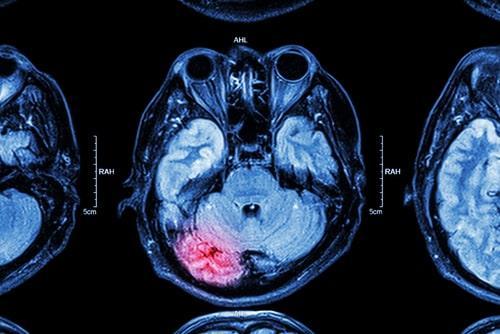

Head injuries are unlike other types of personal injury in that even a seemingly minor accident can have life-altering consequences. When a victim’s head is struck or moved in a violent or sudden manner, the brain may bump against the skull, causing severe injury. Brain injuries are often caused by car, truck, and motorcycle accidents, but they can also be caused by falls, workplace accidents, and more.

Types of Traumatic Brain Injuries

There are a few types of brain injuries that can be caused by an accident. Concussions are among the most common brain injuries. A concussion occurs when a force—such as an abruptly stopping vehicle—causes the head to violently accelerate and stop. Concussions can cause pain, blurred vision, confusion, memory loss, and nausea. Direct trauma brain injuries occur when a person’s skull comes into contact with a hard surface, such as during a slip and fall accident. Indirect trauma can be caused by whiplash, traffic accidents, and more. The resulting nerve damage from an injury such as this can cause brain damage and even death. A diffuse axonal injury occurs when the fibers which connect the brain and nerve cells are damaged. Brain injuries can also occur when the brain is deprived of oxygen. Exposure to toxic substances in an unsafe work environment is one-way hypoxia injuries occur.